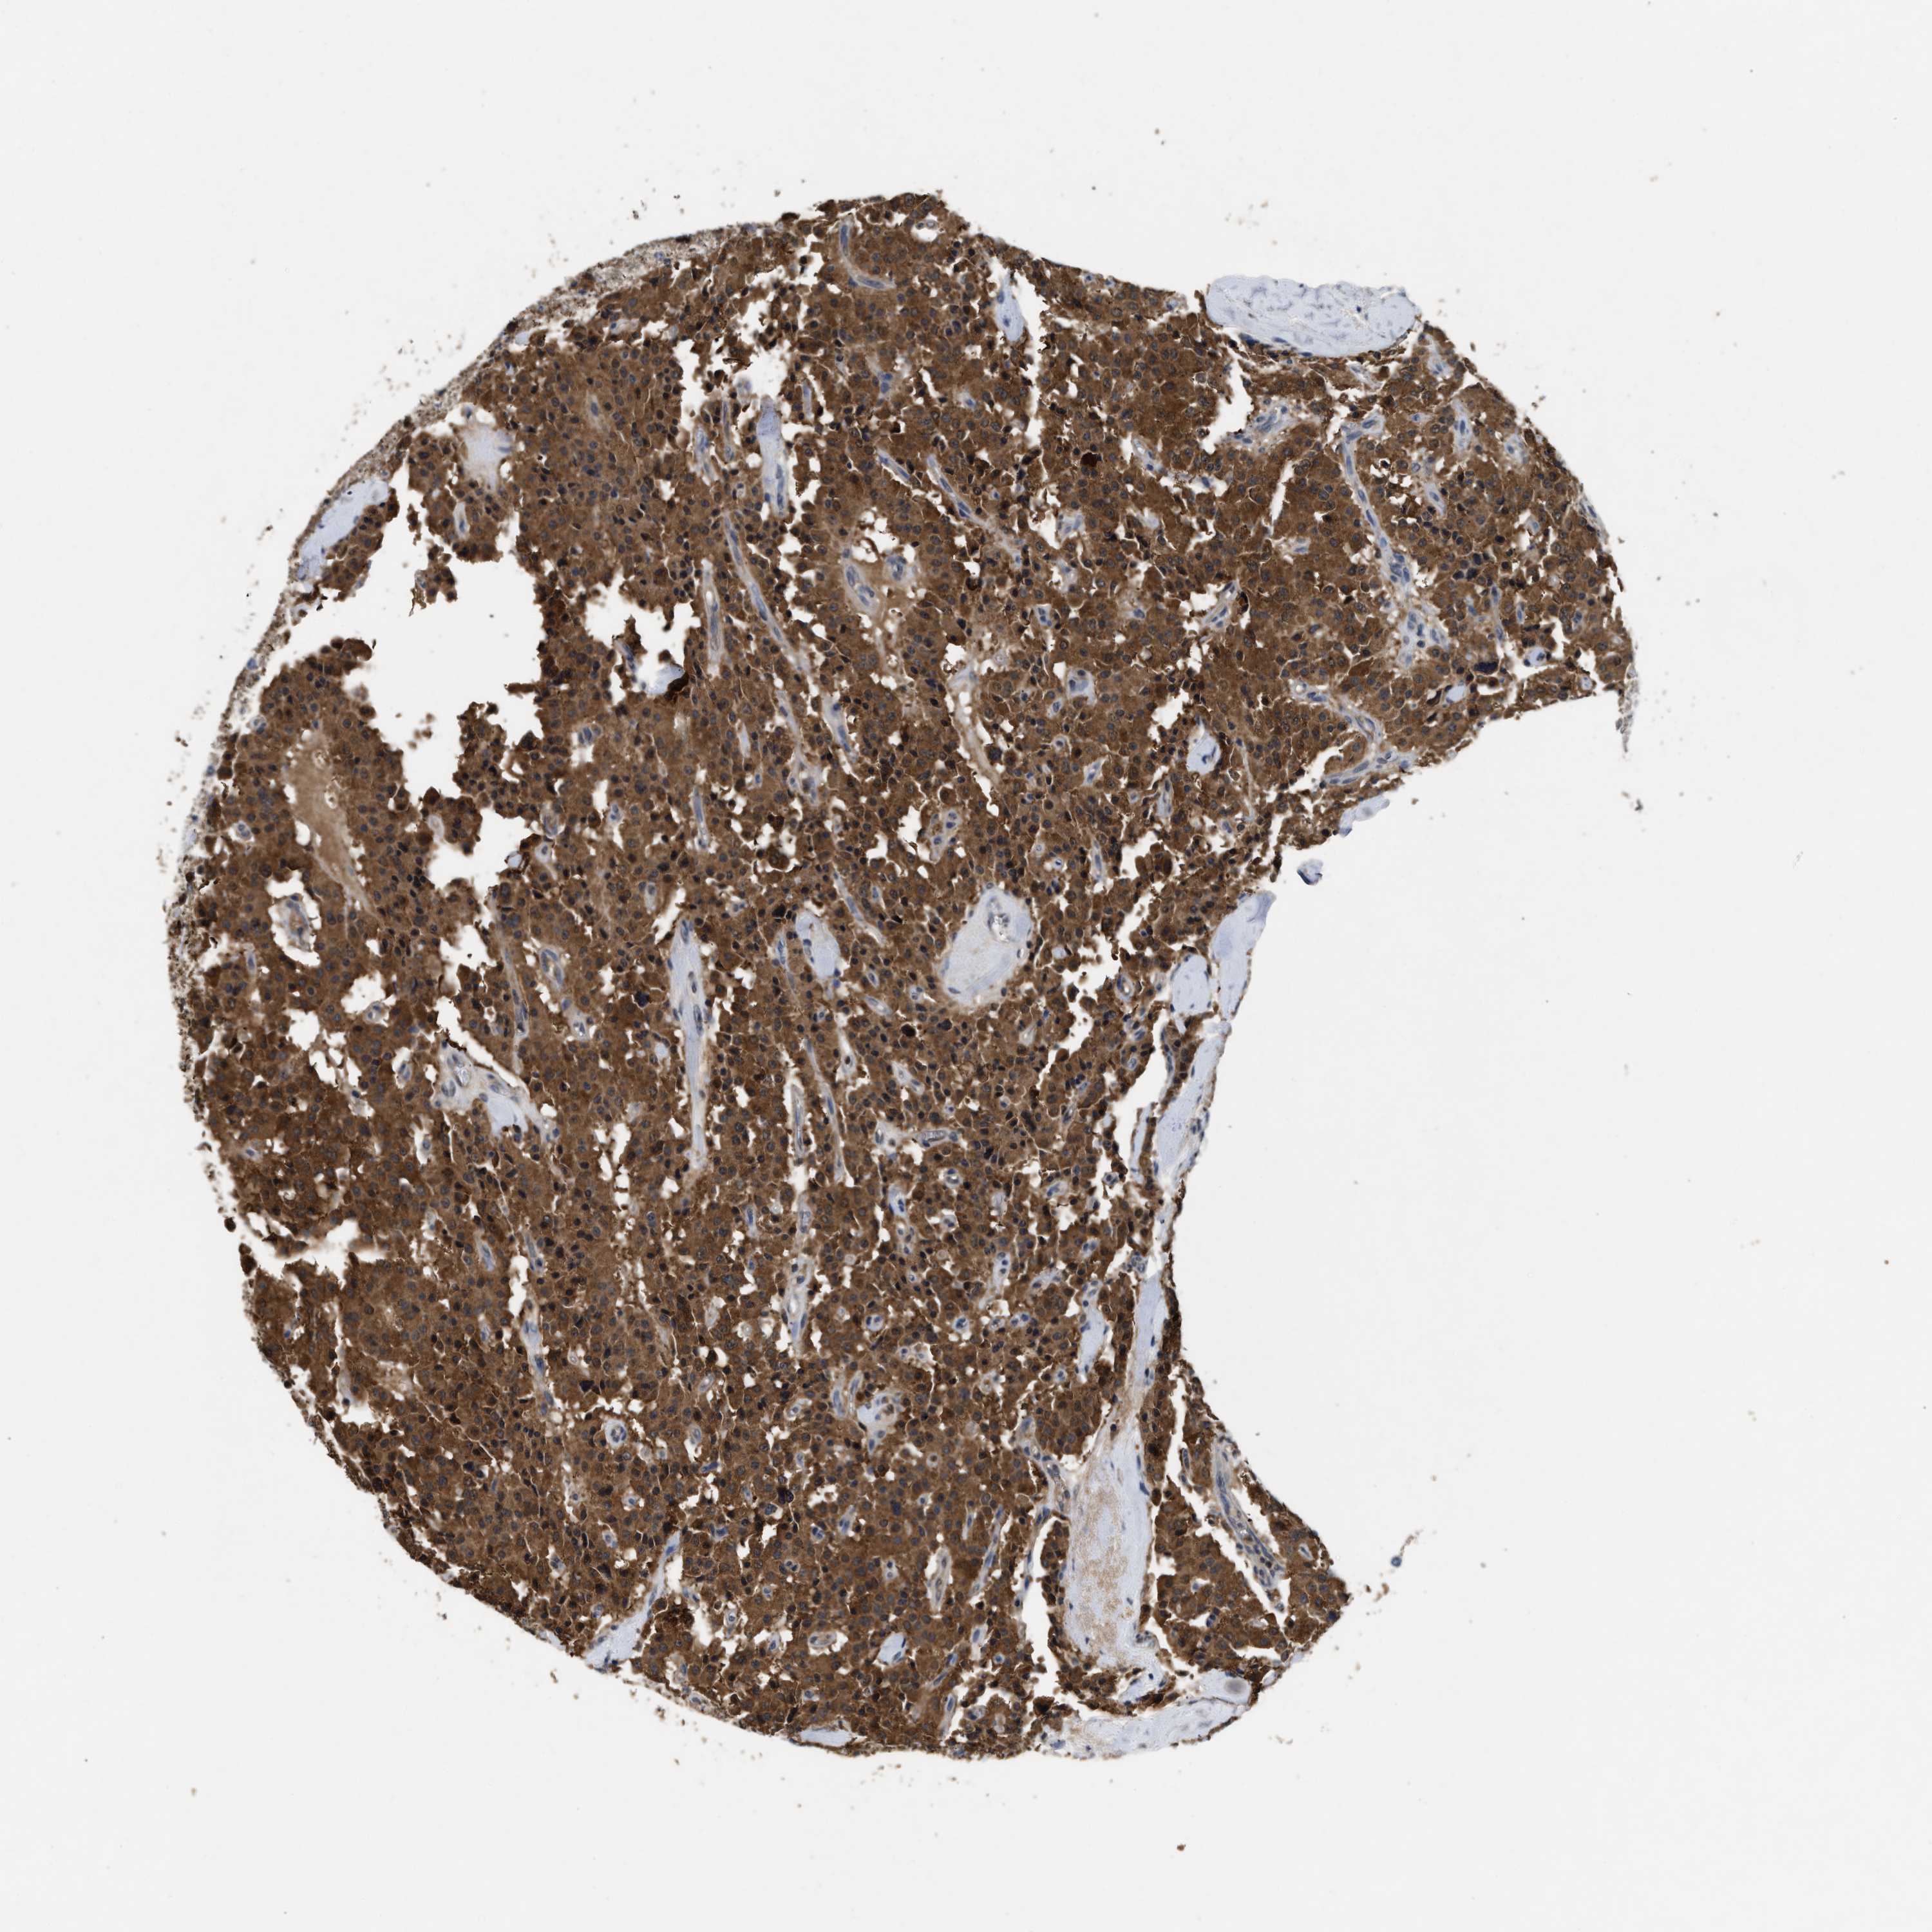

CARCINOID - Protein expressioni

A mouse-over function shows sample information and annotation data. Click on an image to view it in a full screen mode. Samples can be filtered based on level of antibody staining by selecting one or several of the following categories: high, medium, low and not detected. The assay and annotation is described here.

Antibody stainingi

Antibody staining in the annotated cell types in the current human tissue is reported as not detected, low, medium, or high, based on conventional immunohistochemistry profiling in selected tissues. This score is based on the combination of the staining intensity and fraction of stained cells.

Each image is clickable and will lead to virtual microscopy that enables deeper exploration of all samples and also displays staining intensity scores, fraction scores and subcellular localization as well as patient and tissue information for each sample.

Antibody HPA025765

Staining

Medium

Intensity

Moderate

Quantity

75%-25%

Location

Cytoplasmic/membranous

Carcinoid, malignant, NOS